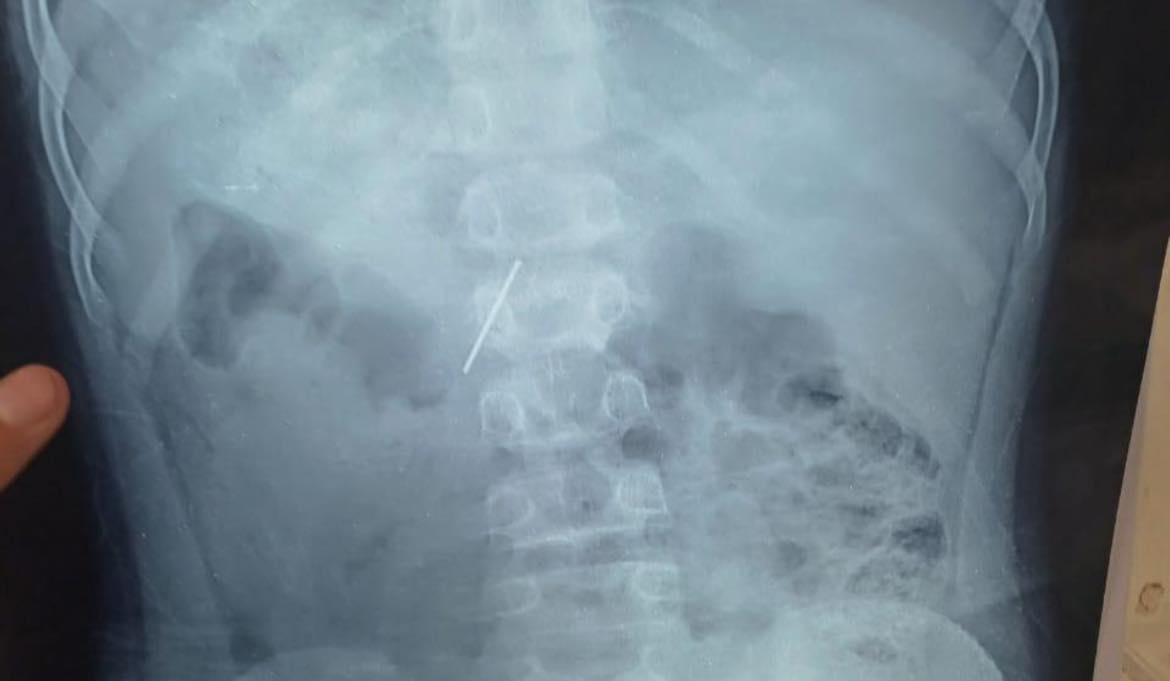

نجح قسم جراحة الأطفال بمستشفى الأطفال التخصصي ببنها في خروج مسمار دباسة كراسي اخترق جدار بطن طفل واستقر داخل التجويف البطني، بعد تدخّل جراحي متقدّم جمع بين المنظار الجراحي وجهاز السي أرم لتحديد الموقع بدقة متناهية.

وصل الطفل إلى المستشفى وهو يعاني ألمًا شديدًا وقلقًا أسرته، وكشفت الفحوصات الأولية وجود جسم غريب حاد داخل البطن. قرار الفريق كان حاسمًا: استئصال المسمار بأسرع وأأمن طريقة ممكنة لتفادي أي مضاعفات قد تهدد حياة المريض.

قاد العملية فريق متميز: د. محمد متولي رئيس قسم جراحة الأطفال، وبمشاركة د. وليد محمد استشاري جراحة الأطفال ود. محمود ممدوح نائب قسم جراحة الأطفال. تم توظيف المنظار الجراحي لتقليل آثار الجراحة والشفاء السريع، فيما لعب جهاز السي أرم دور الخريطة الحية لتحديد موقع المسمار بدقة مدهشة، ما حول العملية إلى مزيج من مهارة الجراح وذكاء الأجهزة.